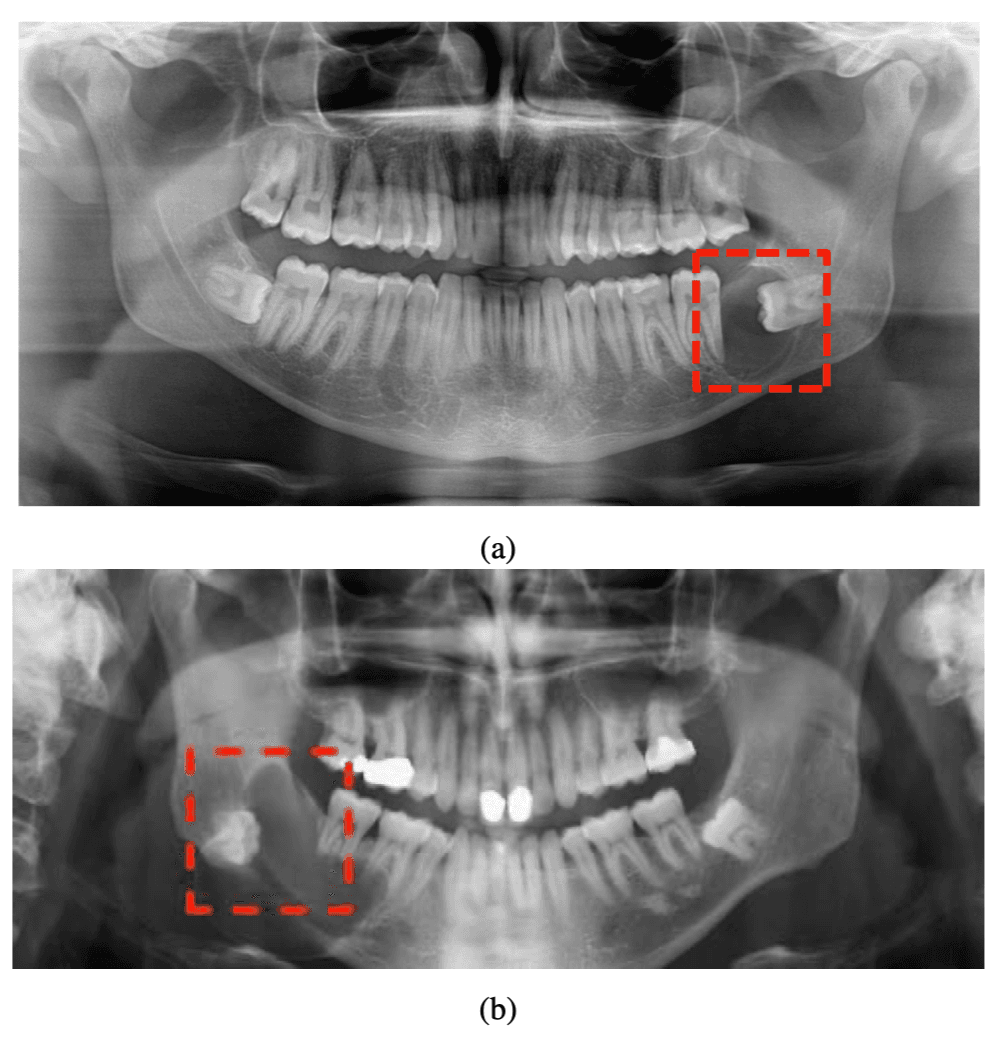

- B.Sc. in Computer EngineeringAmirkabir University of TechnologyB.Sc. Thesis: Design of a Dentigerous Lesion Detection System from Radiographic Images Using Deep Learning

Hybrid Attention Vision Transformer for Dentigerous Cyst Detection (HA-ViT)

- Proposed a hybrid ViT pipeline for dentigerous cyst detection in panoramic dental radiography using dual-path learning (global image + lesion-focused region), achieving 94.44% accuracy, 90.64% sensitivity, 96.74% specificity, and AUC-ROC 0.9829.

Hybrid Vision Transformer for Detection of Dentigerous Cysts in Dental Radiography Images